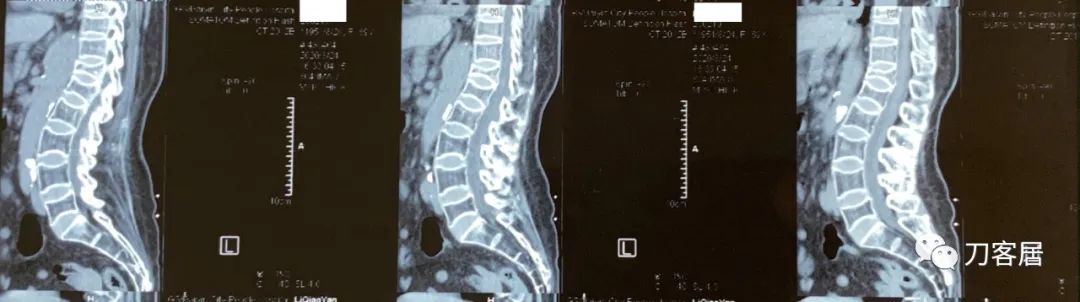

图09-20200824白银市人民医院腰椎CT